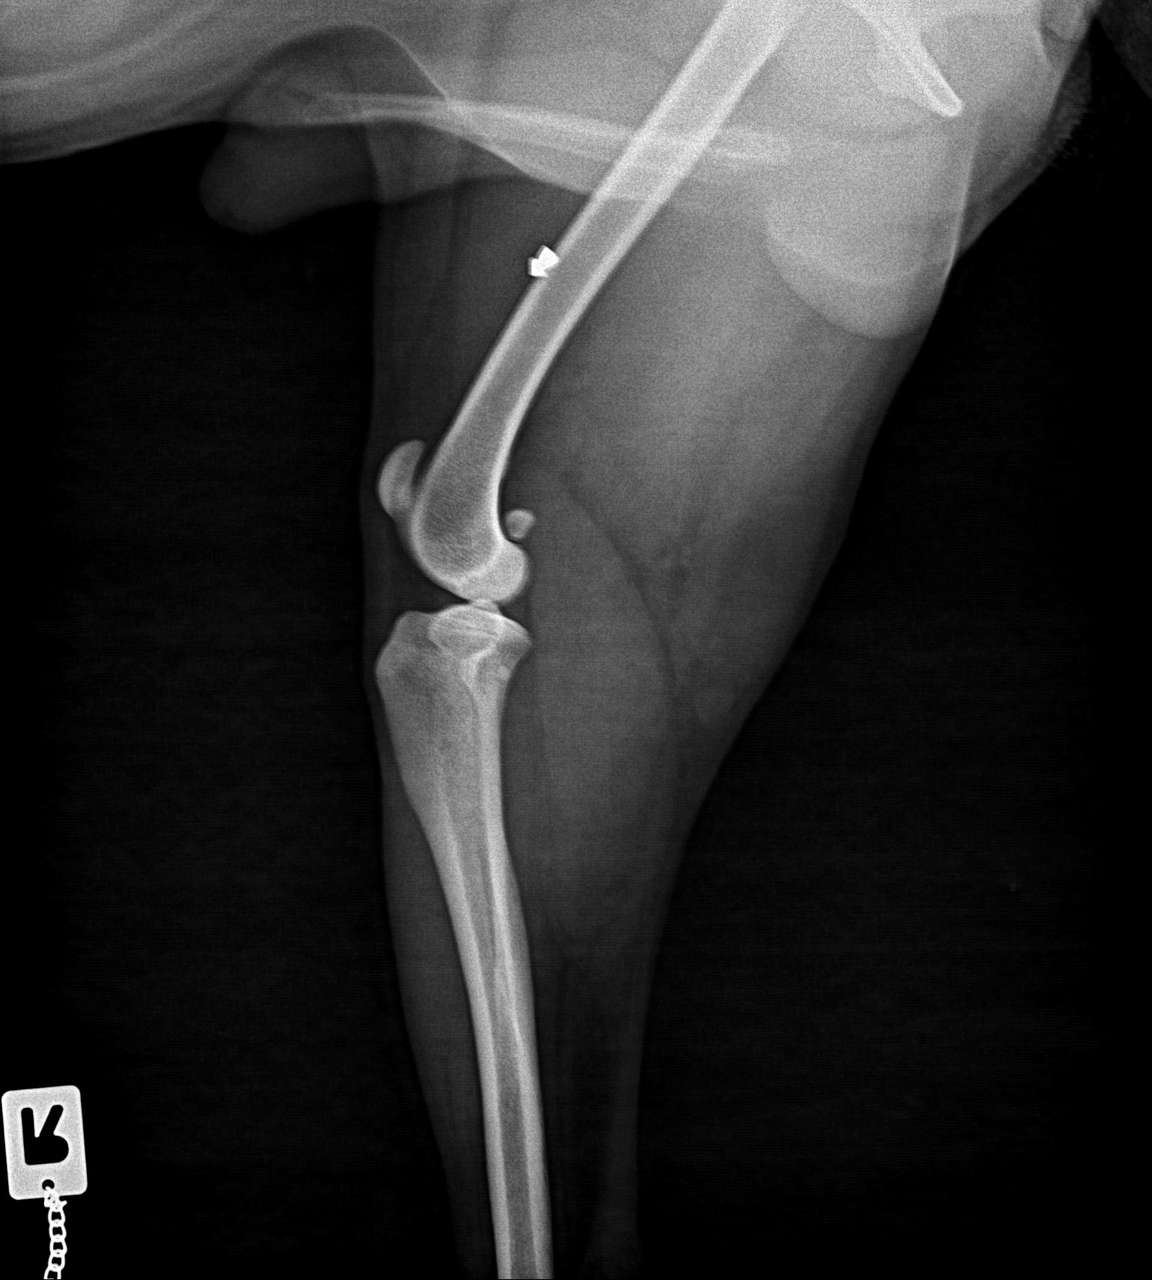

Auf den Röntgenbildern zeigten sich dann zwei Geschosse: Diabolos aus Luftgewehren - eines im Bauchraum und eines im Bein.

Dummerweise sitzt das eine im Bein im Muskel. An diese OP traut sich nicht jeder Tierarzt heran.